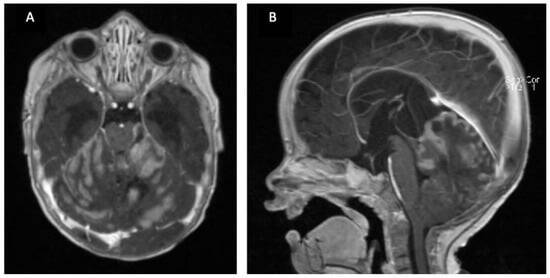

Brain Tumor